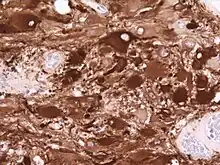

Les tumeurs primaires du SNC comprennent une variété d'entités pathologiques, chacune avec sa propre histoire naturelle. Du fait que les tumeurs gliales représentent à elles seules près de 40 % de ces tumeurs, on peut d'abord distinguer les tumeurs gliales (gliomes) des tumeurs non gliales. Les gliomes les plus courants sont les astrocytomes (provenant des cellules astrocytaires gliales), les oligodendrogliomes (provenant des cellules oligodendrogliales) et les épendymomes (provenant des cellules épendymaires).

Astrocytome

Divers systèmes de catégories ont été proposés dans la littérature au fil du temps pour classer la malignité des astrocytomes. Depuis 1993, le système d'évaluation à quatre niveaux proposé par l' Organisation mondiale de la santé (OMS) est le plus largement utilisé et appliqué. Elle est basée sur quatre caractéristiques histologiques : augmentation de la densité cellulaire, mitose, prolifération endothéliale et nécrose. Par la suite, les astrocytomes de grade I, tels que les astrocytomes pilocytiques, sont généralement d'histologie bénigne. Astrocytomes II. Les grades (diffus) montrent une densité cellulaire accrue comme seule caractéristique histologique et sont des néoplasmes avec un degré d'infiltration inférieur. Les astrocytomes III montrent une mitose importante. grade (anaplasique). Et la prolifération ou la nécrose endothéliale sont observées dans les astrocytomes IV. degrés, les soi-disant glioblastomes.

L'astrocytome anaplasique est une tumeur cérébrale maligne caractérisée par une croissance diffuse, une densité cellulaire accrue et des figures de division nucléaire. Elle est issue d'une population cellulaire spécifique du système nerveux central, les astrocytes. Selon la classification OMS des tumeurs du système nerveux central, la tumeur correspond à une tumeur de grade III.

Les tumeurs des cellules gliales les plus courantes et les plus malignes sont les glioblastomes. Ils consistent en une masse hétérogène de cellules d'astrocytome peu différenciées principalement chez l'adulte. Ils surviennent généralement dans les hémisphères cérébraux, plus rarement dans le tronc cérébral ou la moelle épinière. Sauf dans de très rares cas, comme toutes les tumeurs cérébrales, elles ne s'étendent pas au-delà des structures du système nerveux central.